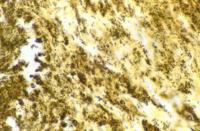

Warthin Starry stain showing B. henselae in cardiac valve of a patient with endocarditis. The bacilli appear as black granulations. Photo courtesy of Pierre Houpikian and Didier Raoult, Unit des Rickettsies, Faculte de Medecine de Marseille, Marseille, France.